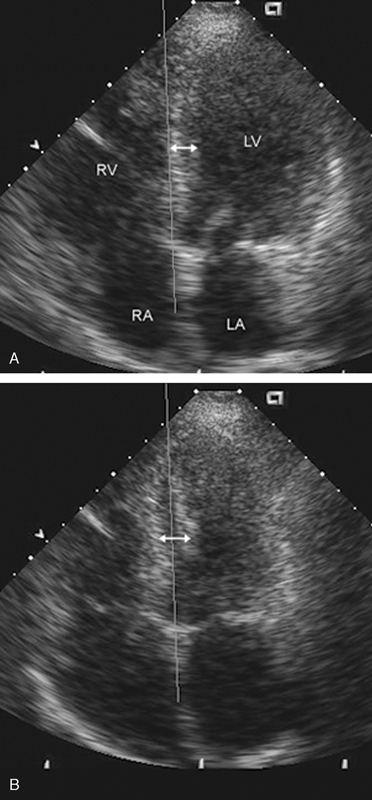

فحوصات تشخيصية لبعض امراض القلب والشرايين التاجية